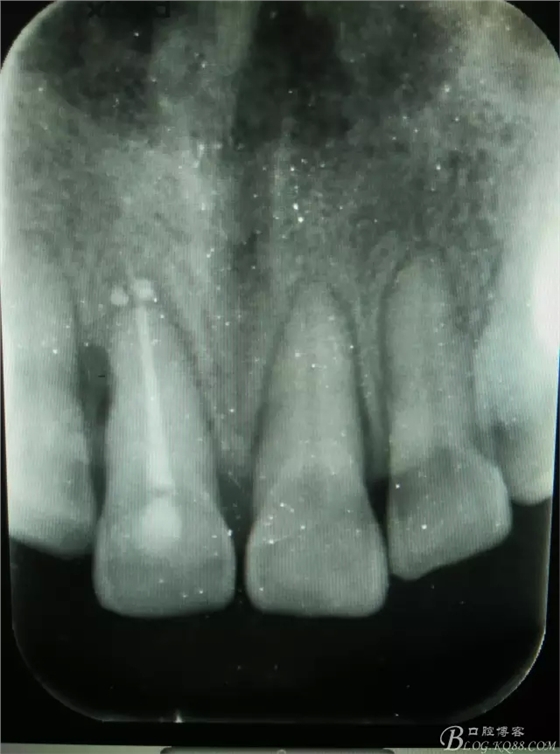

圖1.術(shù)前根尖片顯示11糊劑和牙膠尖均超填,根尖區(qū)及近中有橢圓骨吸收